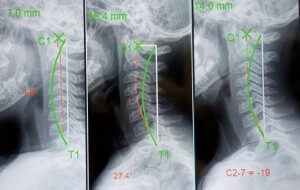

CBP care at Green Chiropractic is guided by objective measurements, not just how you feel on a given day. We use precise X-ray analysis and postural assessments to track changes in your spinal curves and alignment over time.

Many patients are encouraged to see their own before-and-after X-rays, which can show clear structural changes alongside improvements in symptoms and function. This scientific, evidence-based approach helps you and your doctor know that your care is creating lasting change, not just masking discomfort.